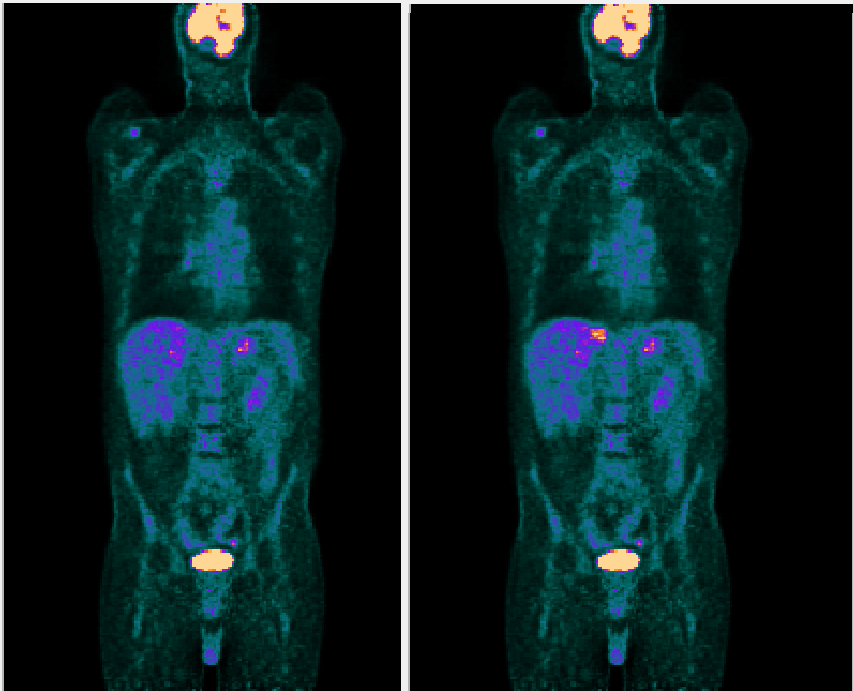

Example FDG PET scan before (left) and after (right) synthesis of a lesion with known size, location and activity.